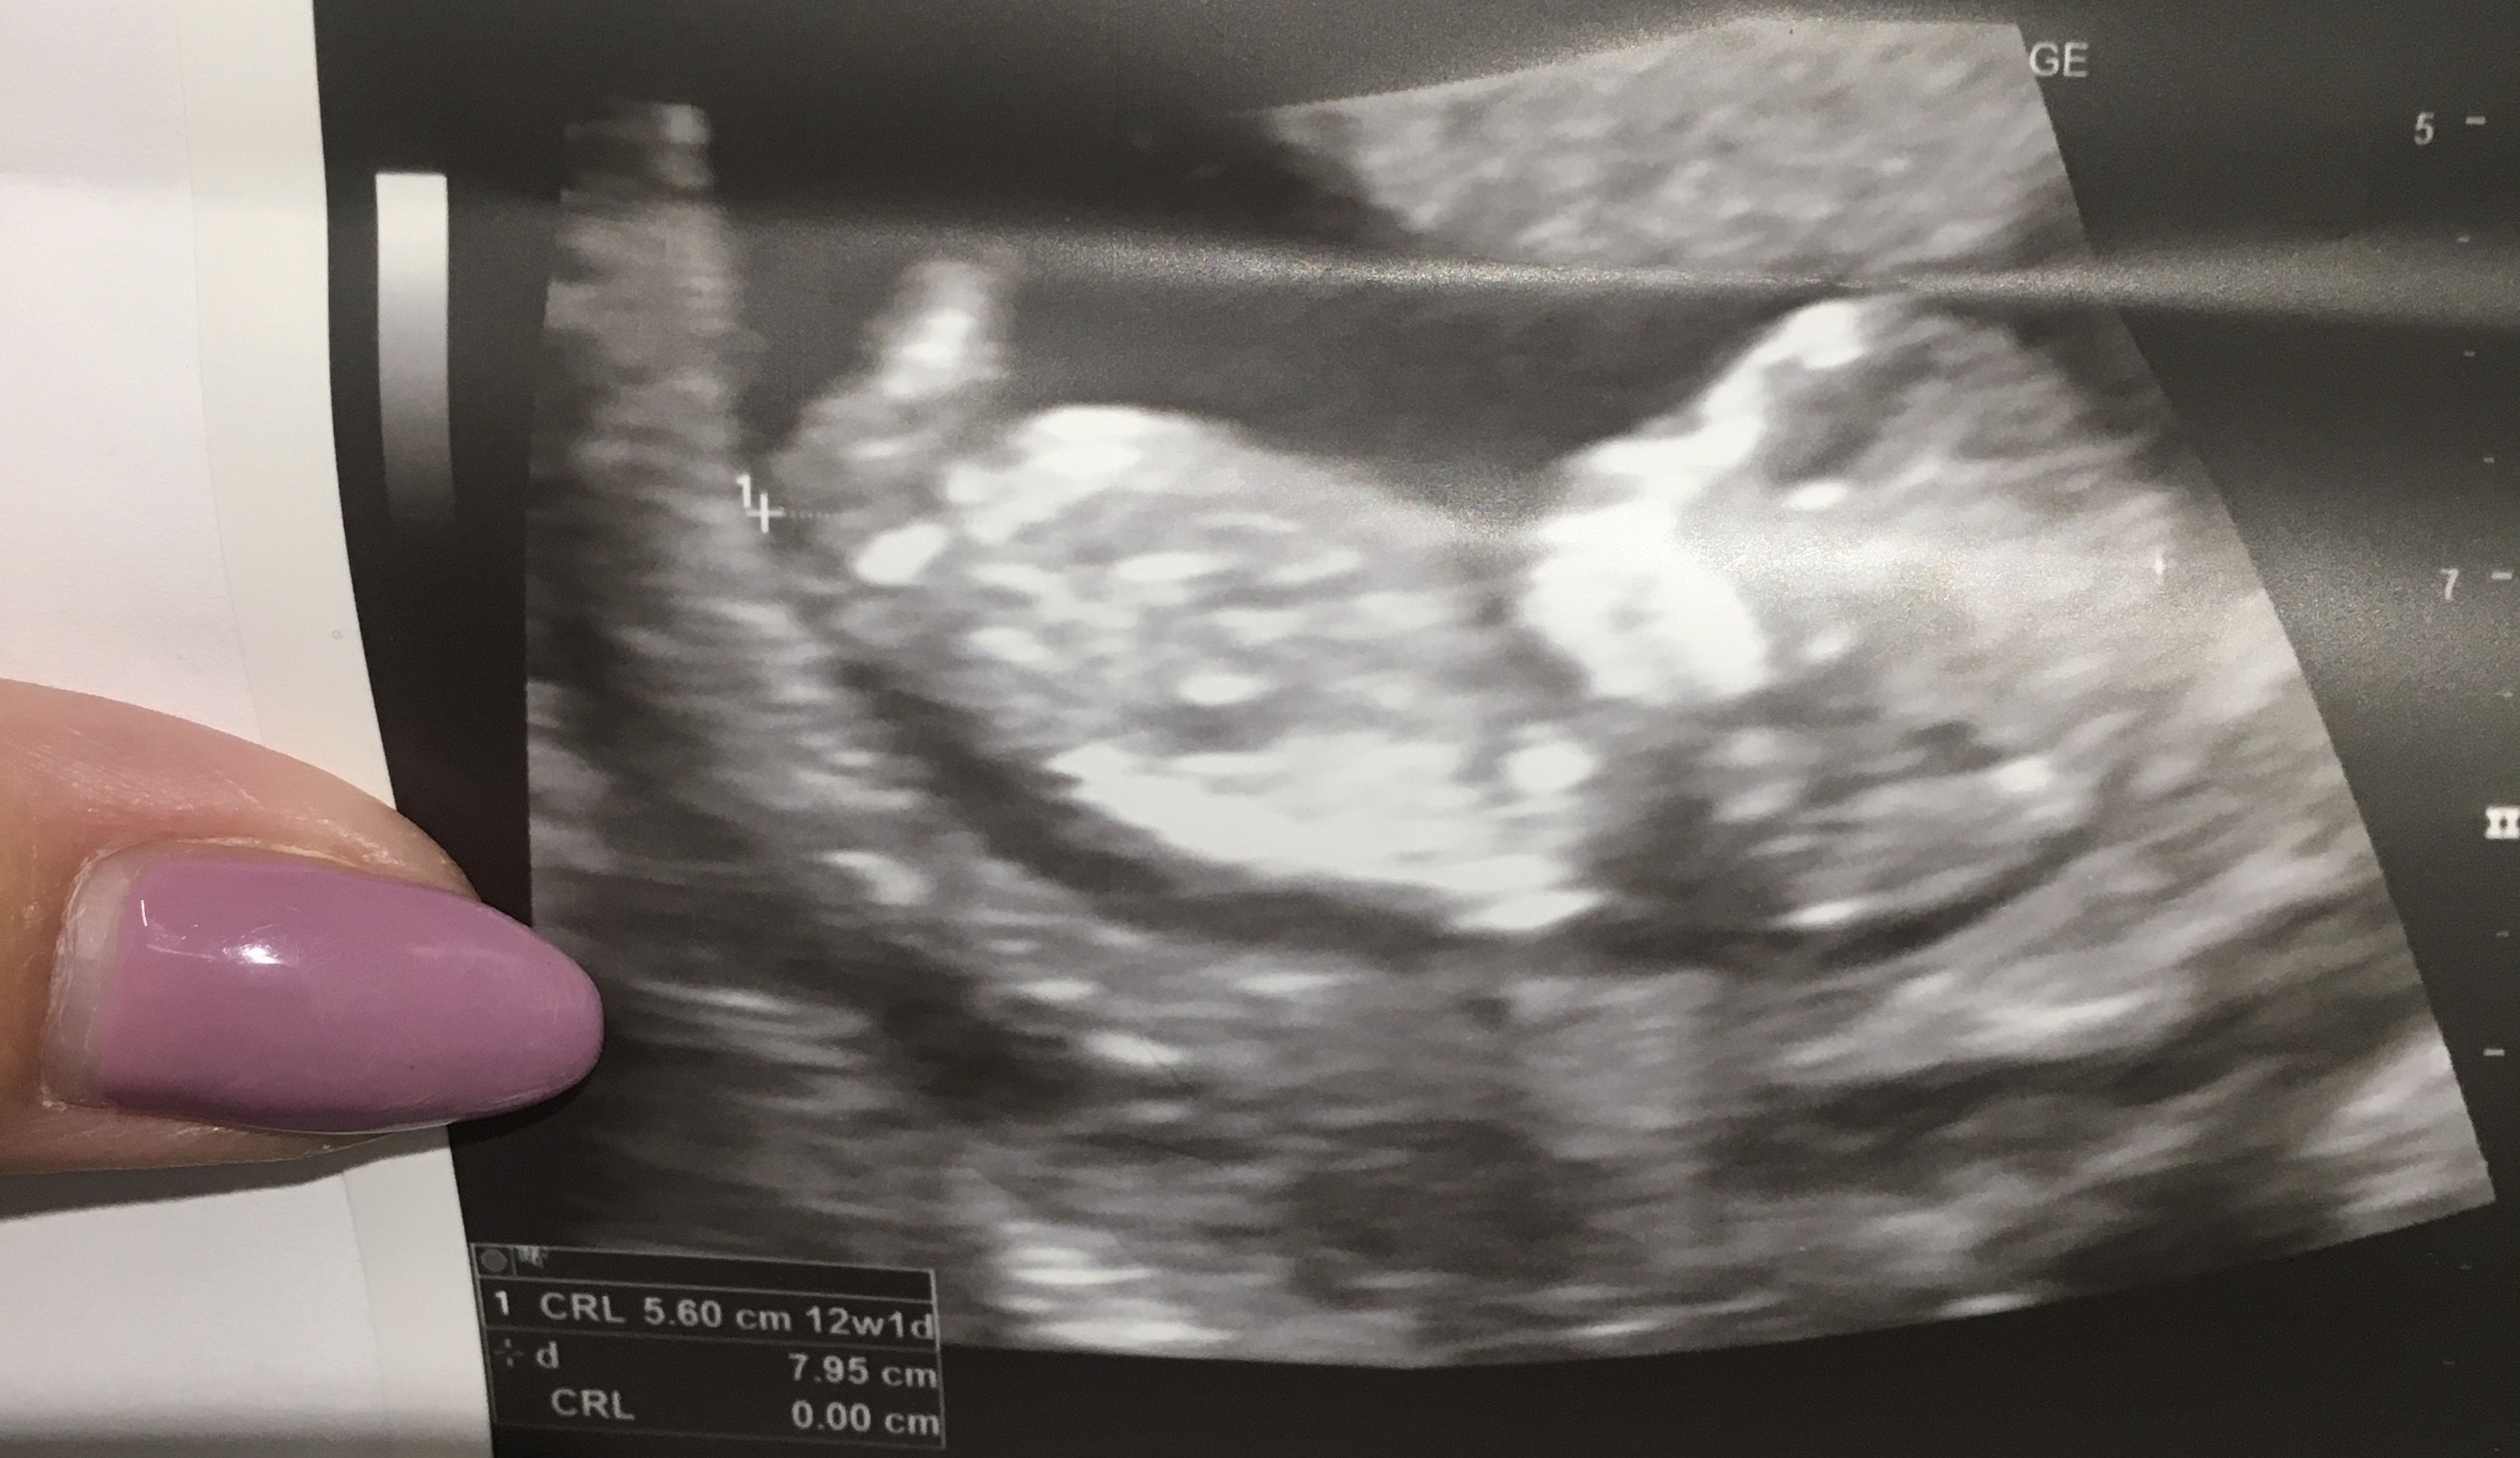

5,5 cm zdrowego dzidziusia ❤️❤️

w poniedziałek prenatalne ☺️☺️

• 24E6308E-EA42-423F-BBEB-53DDF62A7687.jpeg